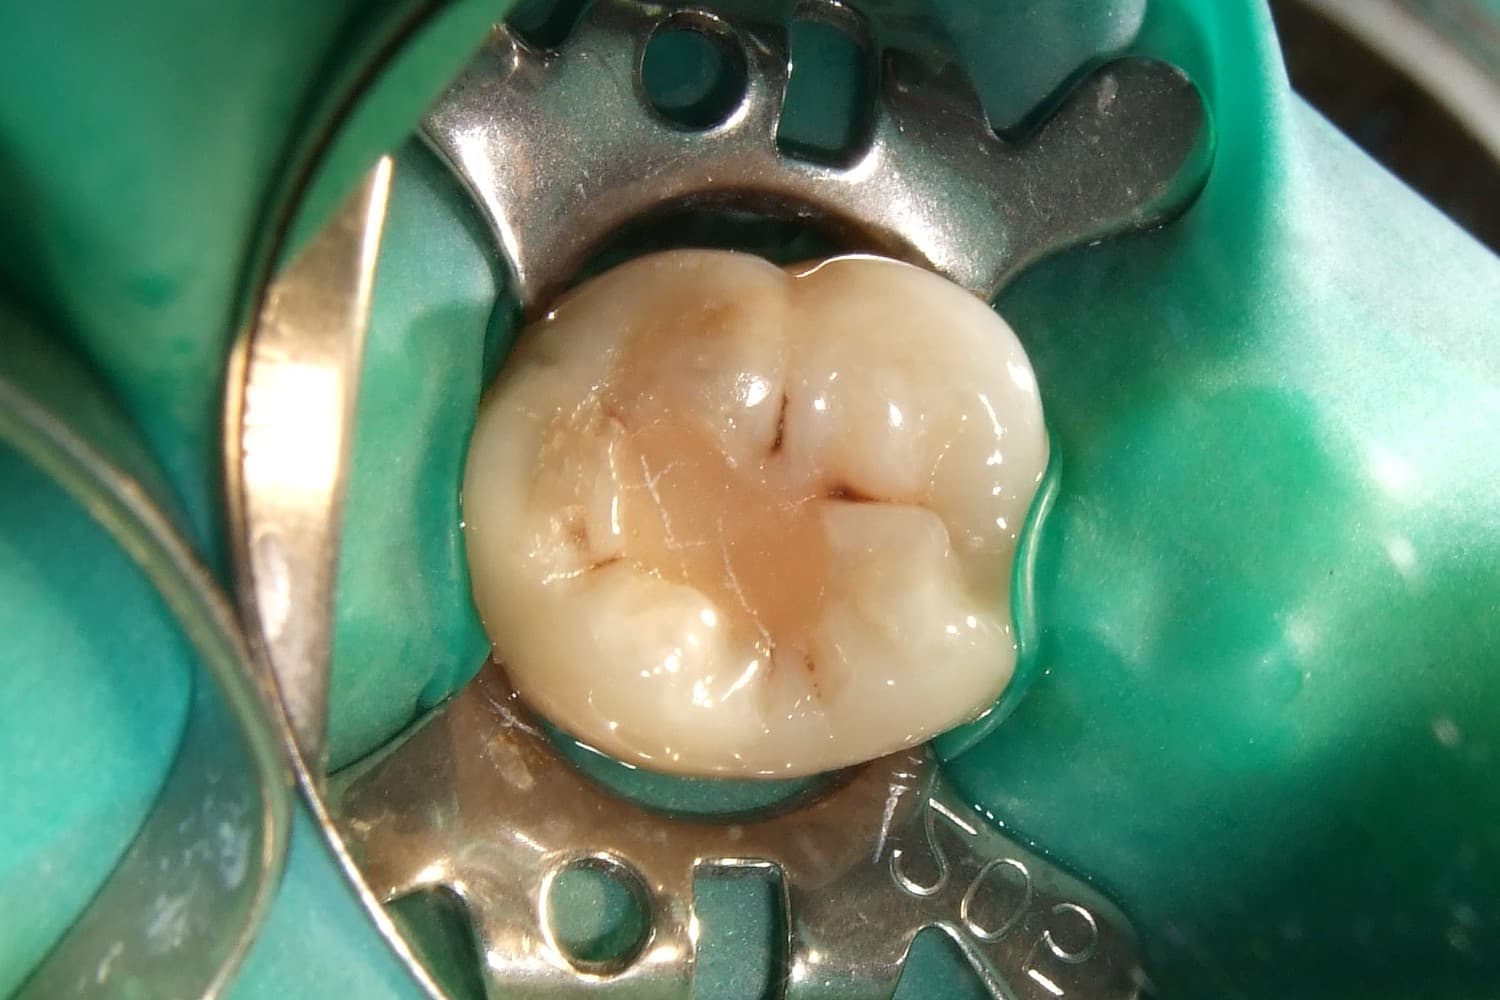

- Yakindan cekilmis agiz ici fotoda eski dolgu alani ve sekonder curuk supheli oluklar not edildi.

- Lokal muayenede restorasyon yenilemesi ile endodontik ihtiyacin ayristirilmasi gerektigi rapora eklendi.